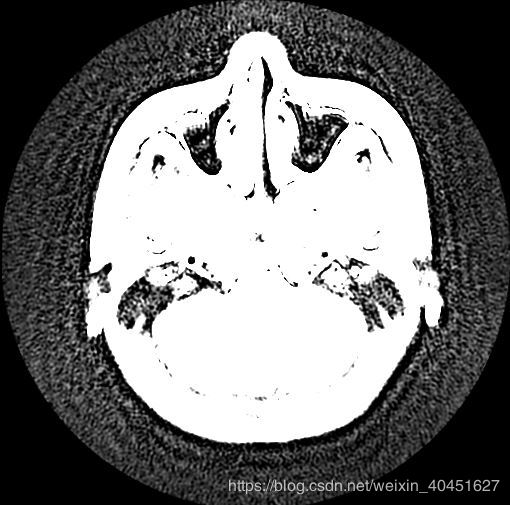

data_img.show()

一條指令即可,但是效果很差,如圖所示:

綜合來看,兩種方法都不是很好.